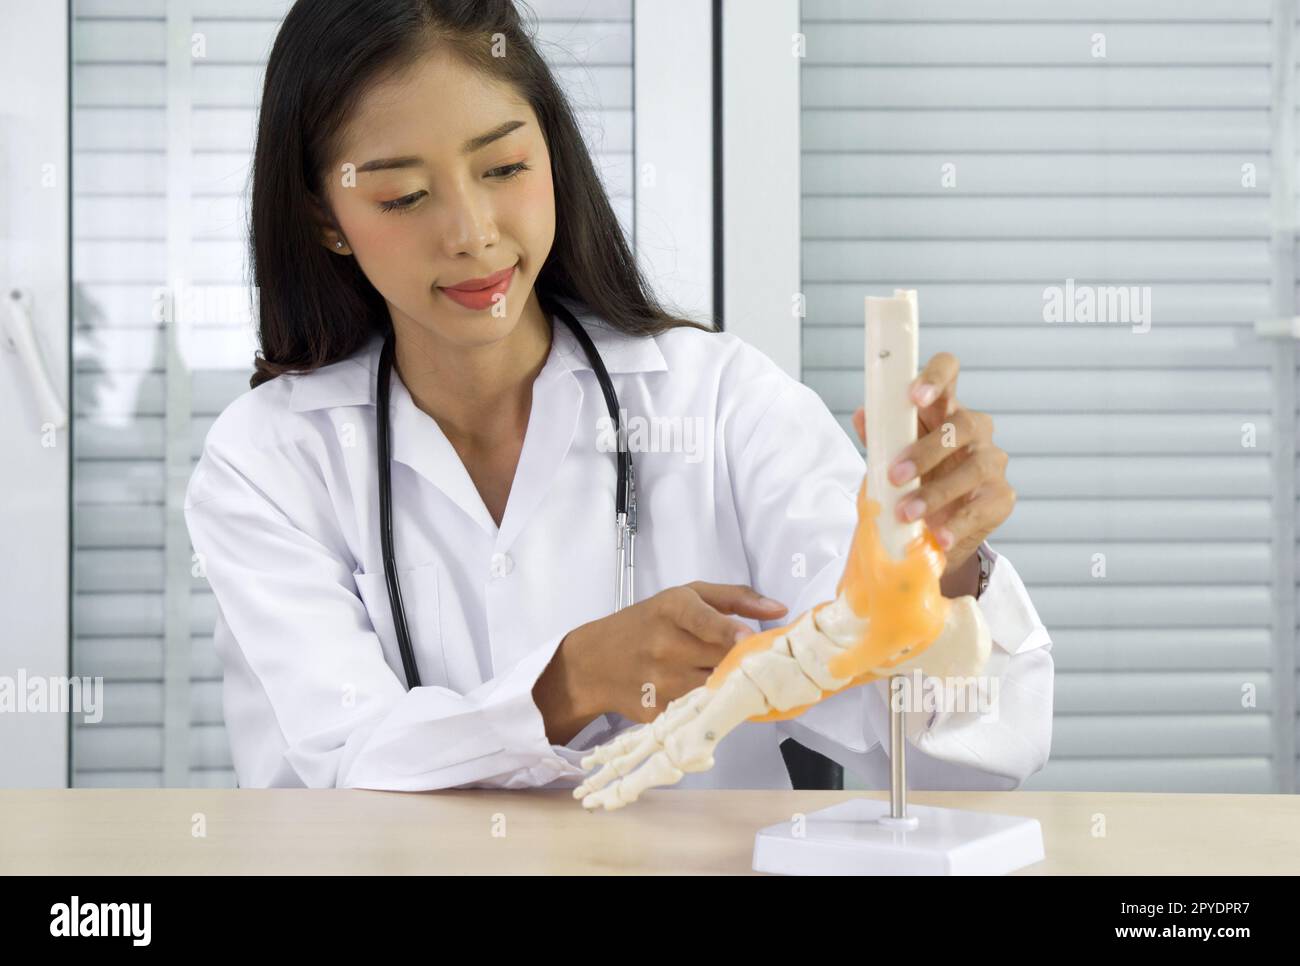

RF2PYDPR7–Jeune médecin asiatique en blouse blanche et stéthoscope pointant vers le squelette humain pied cheville os modèle d'anatomie articulaire, présenté au patient via une communication sans fil. Concept de santé et de médecine.